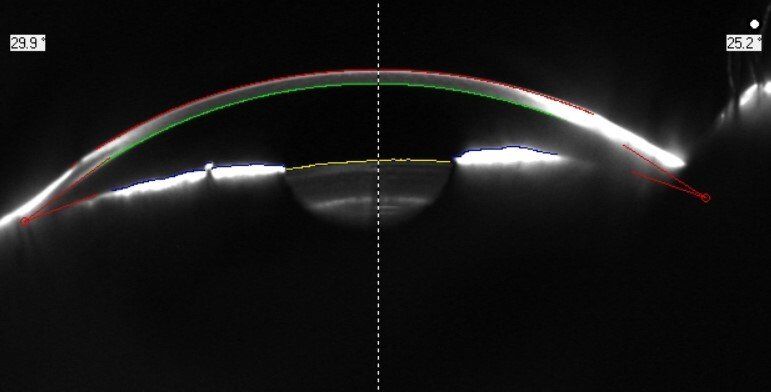

Hier sehen Sie eine Auswahl unserer innovativen Diagnosegeräte, die präzise Analysen ermöglichen und eine frühzeitige Erkennung von Augenerkrankungen unterstützen. Klicken Sie auf „Weiteres“, um Informationen zu den einzelnen Geräten zu erhalten.